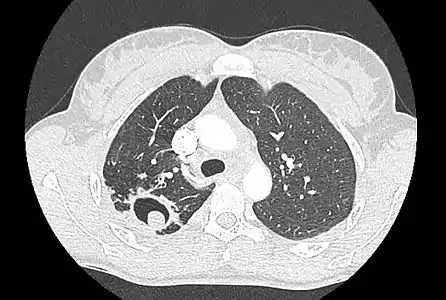

Sur la radiographie pulmonaire, un aspergillome simple apparaît comme un nodule dense, le plus souvent entouré d'un croissant aérique[11]. La radiographie seule ne suffit pas au diagnostic ; un scanner est recommandé[29]. Sur le scanner thoracique, le centre de la cavité est occupé par l'aspergillome[58]. La pseudo-tumeur bouge dans la cavité lorsque le patient change de position (signe de Monod)[58]. Dans l'aspergillome simple, il n'y a pas d'évolution entre les examens et la paroi de la cavité est le plus souvent fine[13]. Un aspergillome complexe[13] présente en revanche l'aspect d'une cavité (ou plusieurs) à parois épaisses, comportant en son centre une truffe aspergillaire. Il existe parfois un début de fibrose pulmonaire[59]. La plèvre adjacente a également un aspect fibrosé, et l'évolution radiologique est lente, mais toujours vers l'aggravation[13]. Un halo en verre dépoli peut également entourer les lésions[45].

Aspect scannographique typique d'un aspergillome développé dans une caverne tuberculeuse.

Le changement de position modifie la position du grelot aspergillaire dans la cavité (signe de Monod).

Le diagnostic radiologique seul n'est cependant pas adapté, d'autres lésions pouvant avoir une présentation similaire (cancer pulmonaire excavé[60],[14] notamment, mais aussi abcès pulmonaire et kyste hydatique[14]). L'injection de produit de contraste iodé, dans le but de mieux visualiser les vaisseaux, permet de dépister un anévrysme de Rasmussen[61], une dilatation pseudo-anévrysmale de l'artère pulmonaire au voisinage d'une cavité intrapulmonaire à risque de rupture, qui entraîne alors une hémoptysie massive souvent fatale[62].